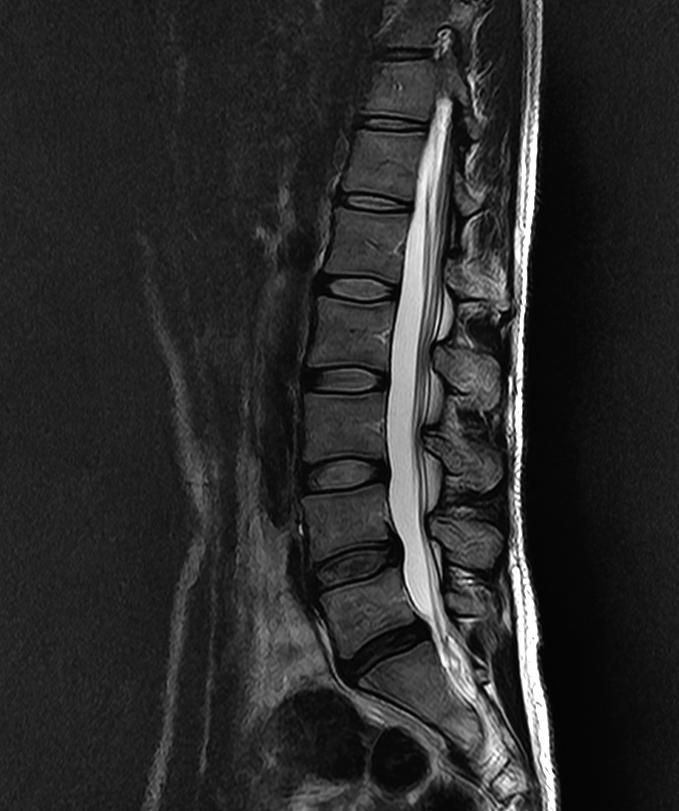

요추 mri 5ㅡ1 디스크입니다.

• 1번 째 사진

• 2번 째 사진